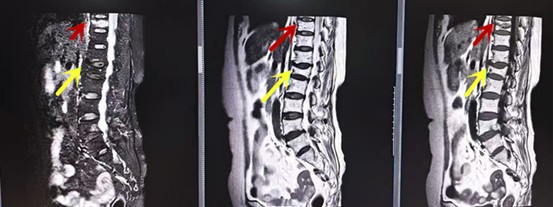

利器三:MRI(核磁共振)

MRI利于磁場(chǎng)和射頻脈沖使體內(nèi)的氫原子核發(fā)生磁共振現(xiàn)象而產(chǎn)生的圖像,對(duì)軟組織的分辨率很高,對(duì)于脊髓、椎間盤、神經(jīng)、血管、韌帶、骨髓、腰部肌肉及周圍軟組織有很好的顯示效果,可以清晰的顯示腰椎間盤突出對(duì)硬膜囊、神經(jīng)根壓迫程度,以及骨折是陳舊還是新鮮,同時(shí)在脊髓病變(如脊髓損傷、髓內(nèi)出血或腫瘤)、椎管內(nèi)膿腫/血腫、椎旁肌肉軟組織病變等方面也具有優(yōu)勢(shì),但是檢查時(shí)間較長(zhǎng),部分患者可能因體內(nèi)金屬植入物(如心臟起搏器、人工耳蝸等)而無法進(jìn)行檢查。

箭頭提示腰椎管內(nèi)腫瘤

紅色箭頭提示新鮮骨折,黃色箭頭提示陳舊性骨折